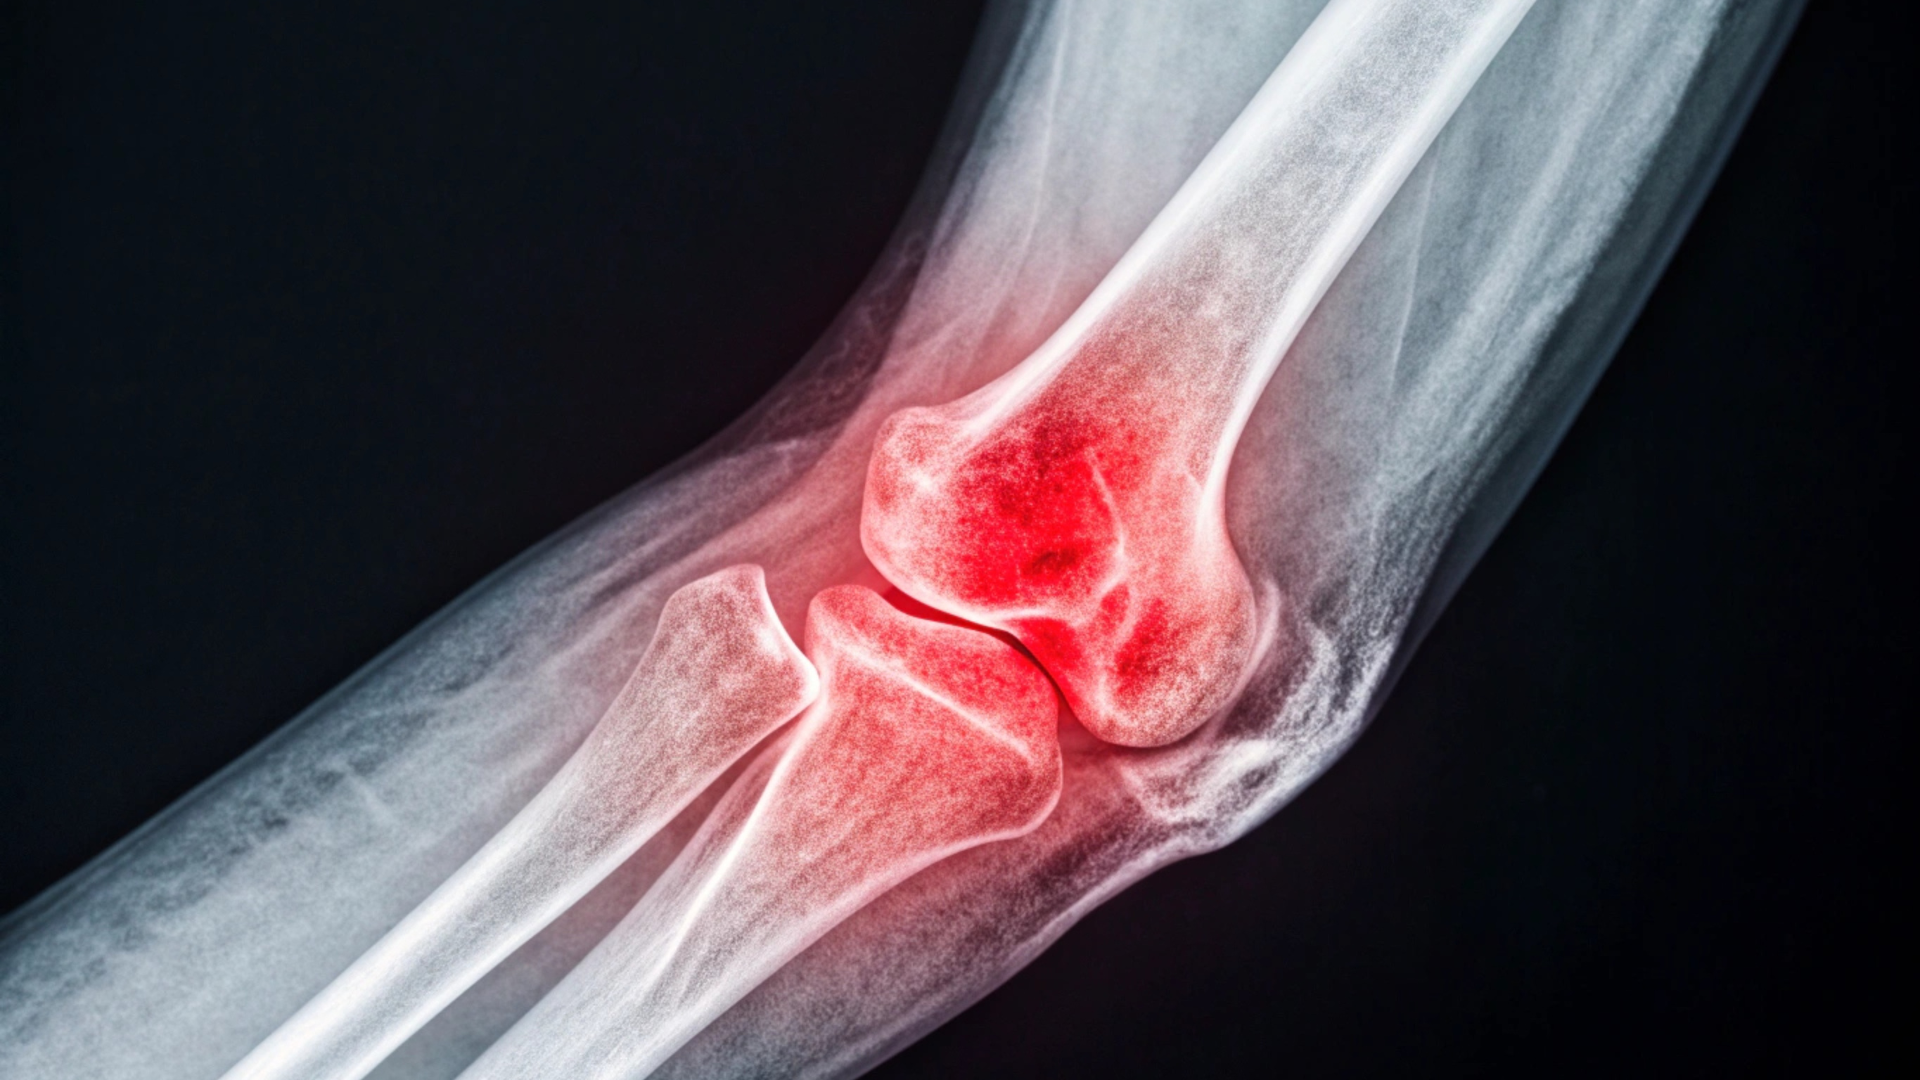

Bong gân ở khuỷu tay là tình trạng dây chằng quanh khớp khuỷu bị kéo giãn quá mức hoặc rách một phần do tác động lực mạnh hoặc vận động sai tư thế. Dây chằng đóng vai trò ổn định khớp và hỗ trợ cử động của cánh tay, vì vậy khi tổn thương, khuỷu tay có thể trở nên đau, yếu hoặc khó vận động.

Tình trạng này có thể xảy ra trong nhiều hoạt động hằng ngày như mang vác vật nặng, ngã chống tay, xoay cánh tay đột ngột hoặc chơi thể thao (nhất là các môn cần lực tay như tennis, bóng rổ, cầu lông). Mức độ bong gân có thể từ nhẹ đến nặng tùy thuộc vào mức độ tổn thương mô mềm.

Trong đa số trường hợp bong gân nhẹ, người bị chấn thương vẫn có thể cử động nhưng sẽ gặp khó khăn khi duỗi thẳng hoặc gập khuỷu tay. Khi tổn thương nặng hơn, khuỷu tay có thể bị sưng rõ, đau nhiều hoặc mất lực ở cánh tay.